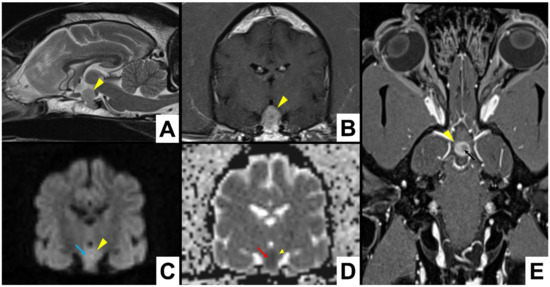

3.4. Imaging Findings

| Signalment | T1-Weighted | T2-Weighted | FLAIR | T2*/SWI | DWI | ADC | Contrast Enhancement | MRI Diagnosis |

|---|---|---|---|---|---|---|---|---|

| 1. Mixed breed MN, 9.75 y, 24.6 Kg | Homogeneous isointense | Heterogeneous isointense | Heterogeneous isointense | No | Hyperintense | Hypointense | Heterogeneous | Pituitary mass with different stages of intralesional haemorrhage |

| 2. Italian hound F, 11.5 y, 14.8 Kg | Heterogeneous isointense | Heterogeneous isointense | Heterogeneous isointense | Yes | Hyperintense | Hypointense | Heterogeneous | Pituitary mass with intralesional haemorrhage |

| 5. Mixed breed FN, 12.7 y, 30 Kg | Homogeneous isointense | Heterogeneous isointense | Heterogeneous isointense | Yes | Isointense | Isointense | Heterogeneous | Pituitary mass with intralesional haemorrhage |

| 6. Beagle FN, 7.6 y, 16.6 Kg | Heterogeneous hypointense | Heterogeneous hyperintense | Heterogeneous hyperintense | Yes | Hypointense | Hypointense | Heterogeneous | Pituitary mass with intralesional haemorrhage |

| 7. Labrador Retriever F, 5 y, 31.2 Kg | Heterogeneous hypointense | Heterogeneous hyperintense | Heterogeneous hyperintense | \ | Hypointense | Hyperintense | Heterogeneous | Pituitary mass with intralesional haemorrhage |

| 8. Labrador Retriever FN, 10.8 y, 35 Kg | Heterogeneous hypointense | Heterogeneous hyperintense | Heterogeneous hyperintense | No | \ | \ | Heterogeneous | Pituitary mass |

| 9. Mixed breed FN, 5.8 y, 21 Kg | Heterogeneous hypointense | Heterogeneous hyperintense | Heterogeneous hyperintense | Yes | \ | \ | Heterogeneous | Pituitary mass with intralesional haemorrhage |

| 11. Boxer FN, 11.4 y, 27.4 Kg | Homogeneous hyperintense | Heterogeneous hyperintense | Heterogeneous hyperintense | \ | \ | \ | Heterogeneous | Pituitary mass with intralesional haemorrhage |

| 12. Springer Spaniel M, 13.7 y, 18.7 Kg | Heterogeneous isointense | Heterogeneous hyperintense | Heterogeneous hyperintense | Yes | Hypointense | Hyperintense | Heterogeneous | Pituitary mass with intralesional haemorrhage |